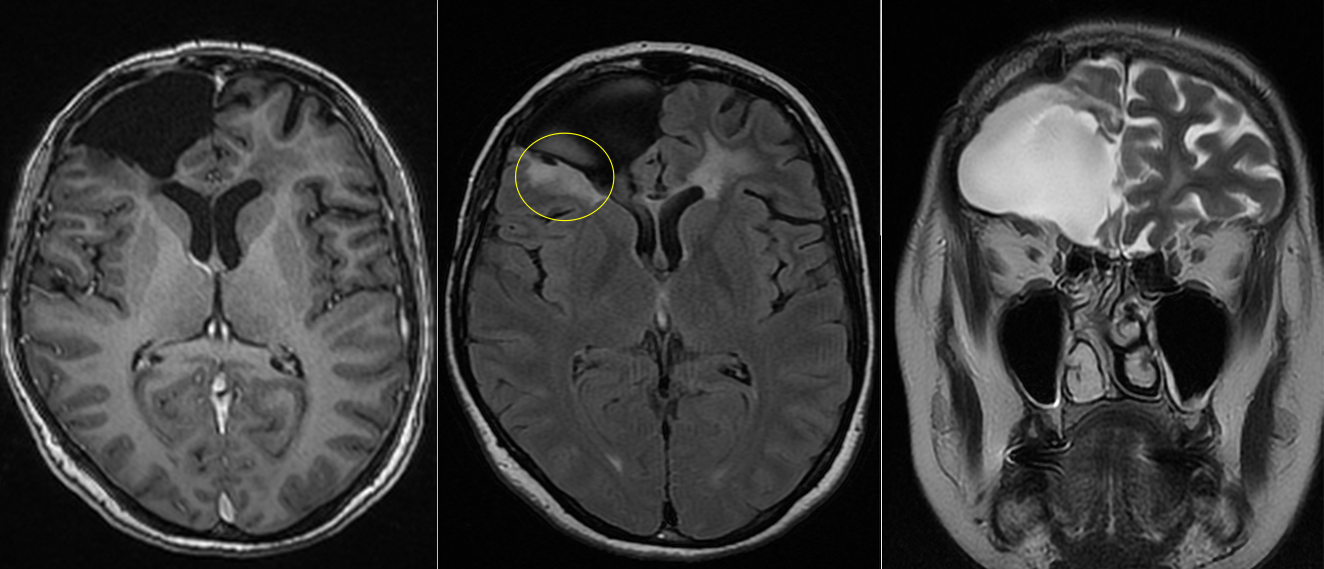

Sub tratamentul chimioterapic, evoluția a fost favorabilă.

RMN-urile succesive au arătat:

- absența progresiei leziunii

- stabilitate imagistică

- lipsa transformării către un fenotip agresiv

- fără progresie tumorală, în condițiile tratamentului intermitent cu Temozolomidă.

- boală controlată imagistic